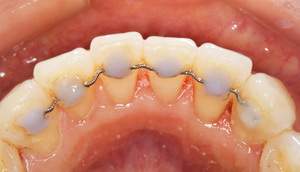

歯石除去

治療前

治療後

| 年齢 | 25歳・男性 |

| 主訴 | 歯石をとりたい・検診 |

| 治療内容 | 各種検査・歯石除去 |

| 治療期間 | 60分 |

| 費用 | 初診料3,000〜4,000円前後 +歯石除去約1,000円 |

| リスク・副作用 | ・処置後に歯がしみることがあります。 ・歯と歯の間に隙間ができるので、息が漏れ発音しにくいと感じることがあります。 ・歯ぐきの炎症が軽減すると歯ぐきが引き締まり、歯が長く見えることがあります。 |

| 担当者所見 | 前歯の裏側にすぐに歯石が溜まってしまいザラザラして気になるとご相談いただいたので適切な歯ブラシの当て方とフロスの通し方をお伝えさせて頂きました。 |